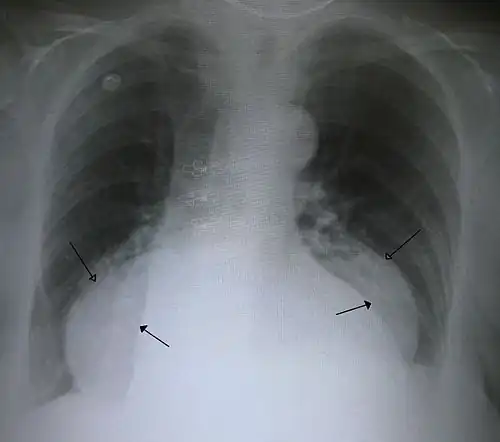

-

A large hiatal hernia on chest X-ray marked by open arrows in contrast to the heart borders marked by closed arrows